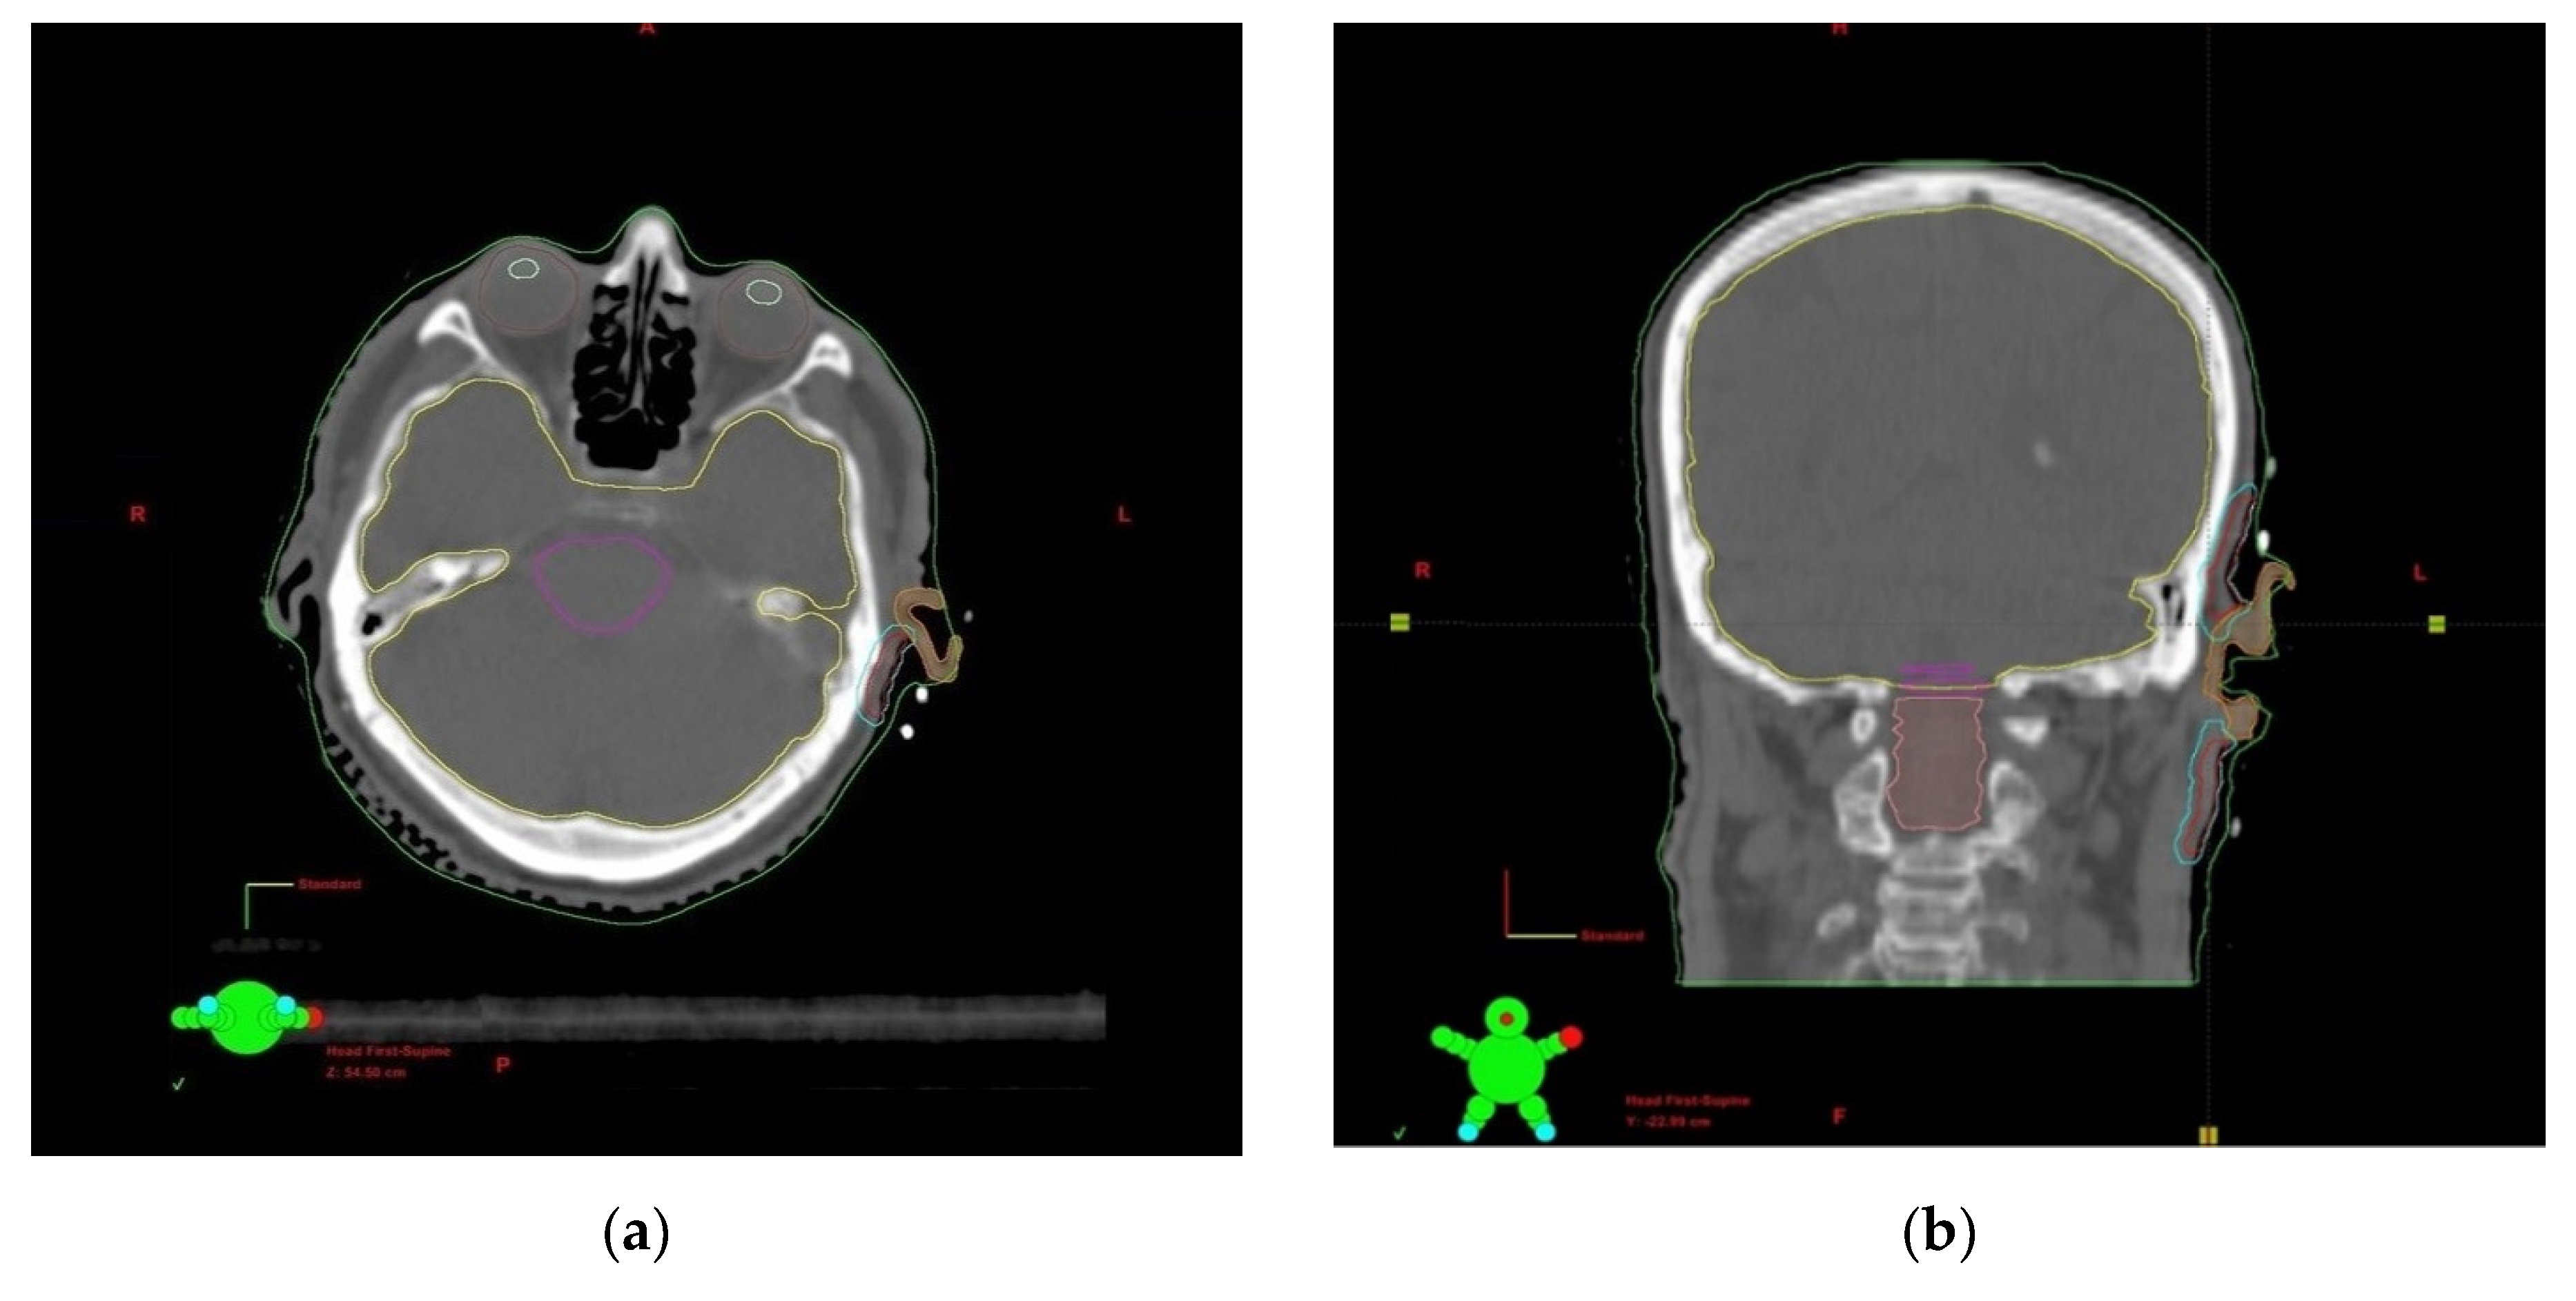

2.2. Procedure, Planning, and Treatment

2.3. Treatment Planning and Dosimetry Analysis